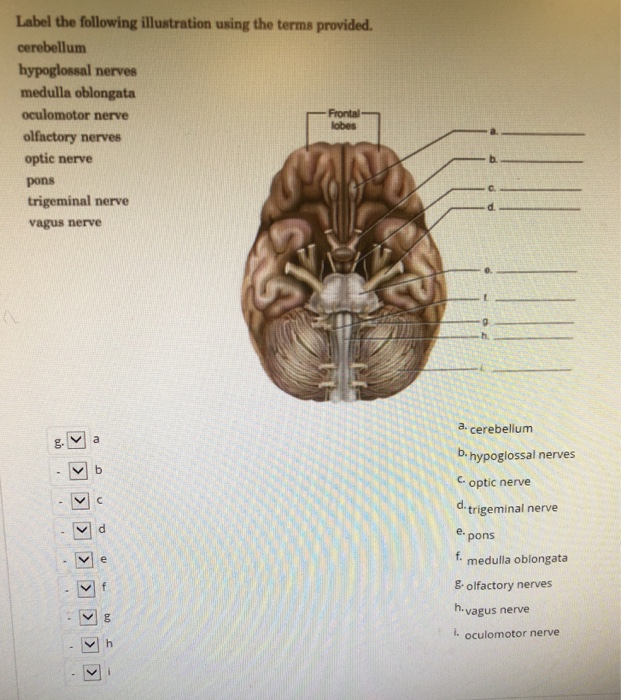

Solved Label the following illustration using the terms | Chegg.com